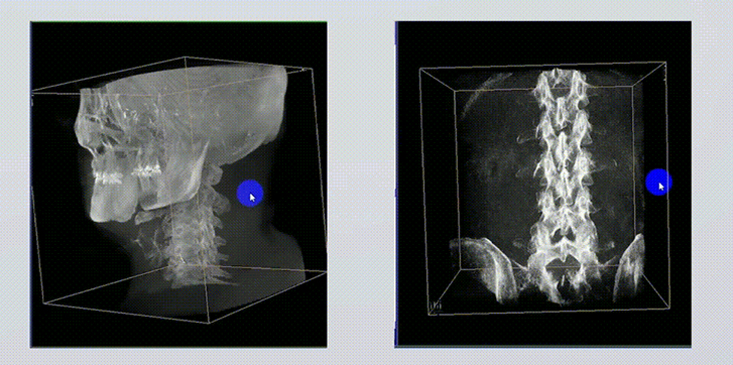

1、術(shù)中實(shí)時(shí)三維成像

術(shù)中三維成像和橫斷面圖像提供多角度的手術(shù)診斷信息,輔助醫(yī)生進(jìn)行術(shù)中評估判斷,諸如骨折復(fù)位情況和內(nèi)植入螺釘?shù)某叽绾臀恢茫o助手術(shù)更好地完成。

2、三維成像視野大

提供更大的術(shù)中三維成像視野,采集更多圖像信息,可一次拍全全段頸椎、全段腰椎、七節(jié)胸椎、雙側(cè)骶髂關(guān)節(jié)、股骨頭及單側(cè)盆骨。